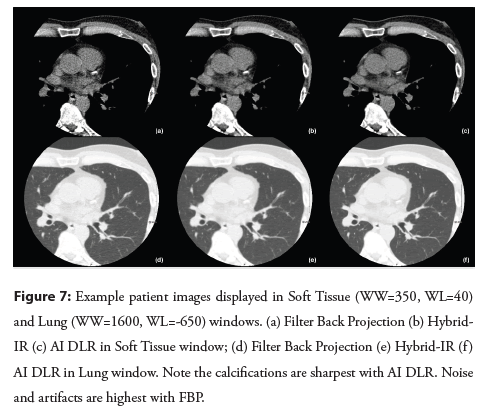

This is supported by qualitative image analysis where individual calcifications may appear sharper and denser on AI DLR and FBP than on Hybrid-IR (Figure 7). It should also be noted that the FBP images have significantly worse clinical diagnostic quality than the AI DLR images and would not be advised for routine clinical use at either soft tissue or lung contrast settings. This is noted in the kappa agreement statistic for minimal calcium classification, which indicates only fair agreement (κ=0.27 ± 0.14) between the Hybrid IR and FBP reconstructions.

Figure 7: Example patient images displayed in Soft Tissue (WW=350, WL=40) and Lung (WW=1600, WL=-650) windows. (a) Filter Back Projection (b) Hybrid- IR (c) AI DLR in Soft Tissue window; (d) Filter Back Projection (e) Hybrid-IR (f ) AI DLR in Lung window. Note the calcifications are sharpest with AI DLR. Noise and artifacts are highest with FBP.